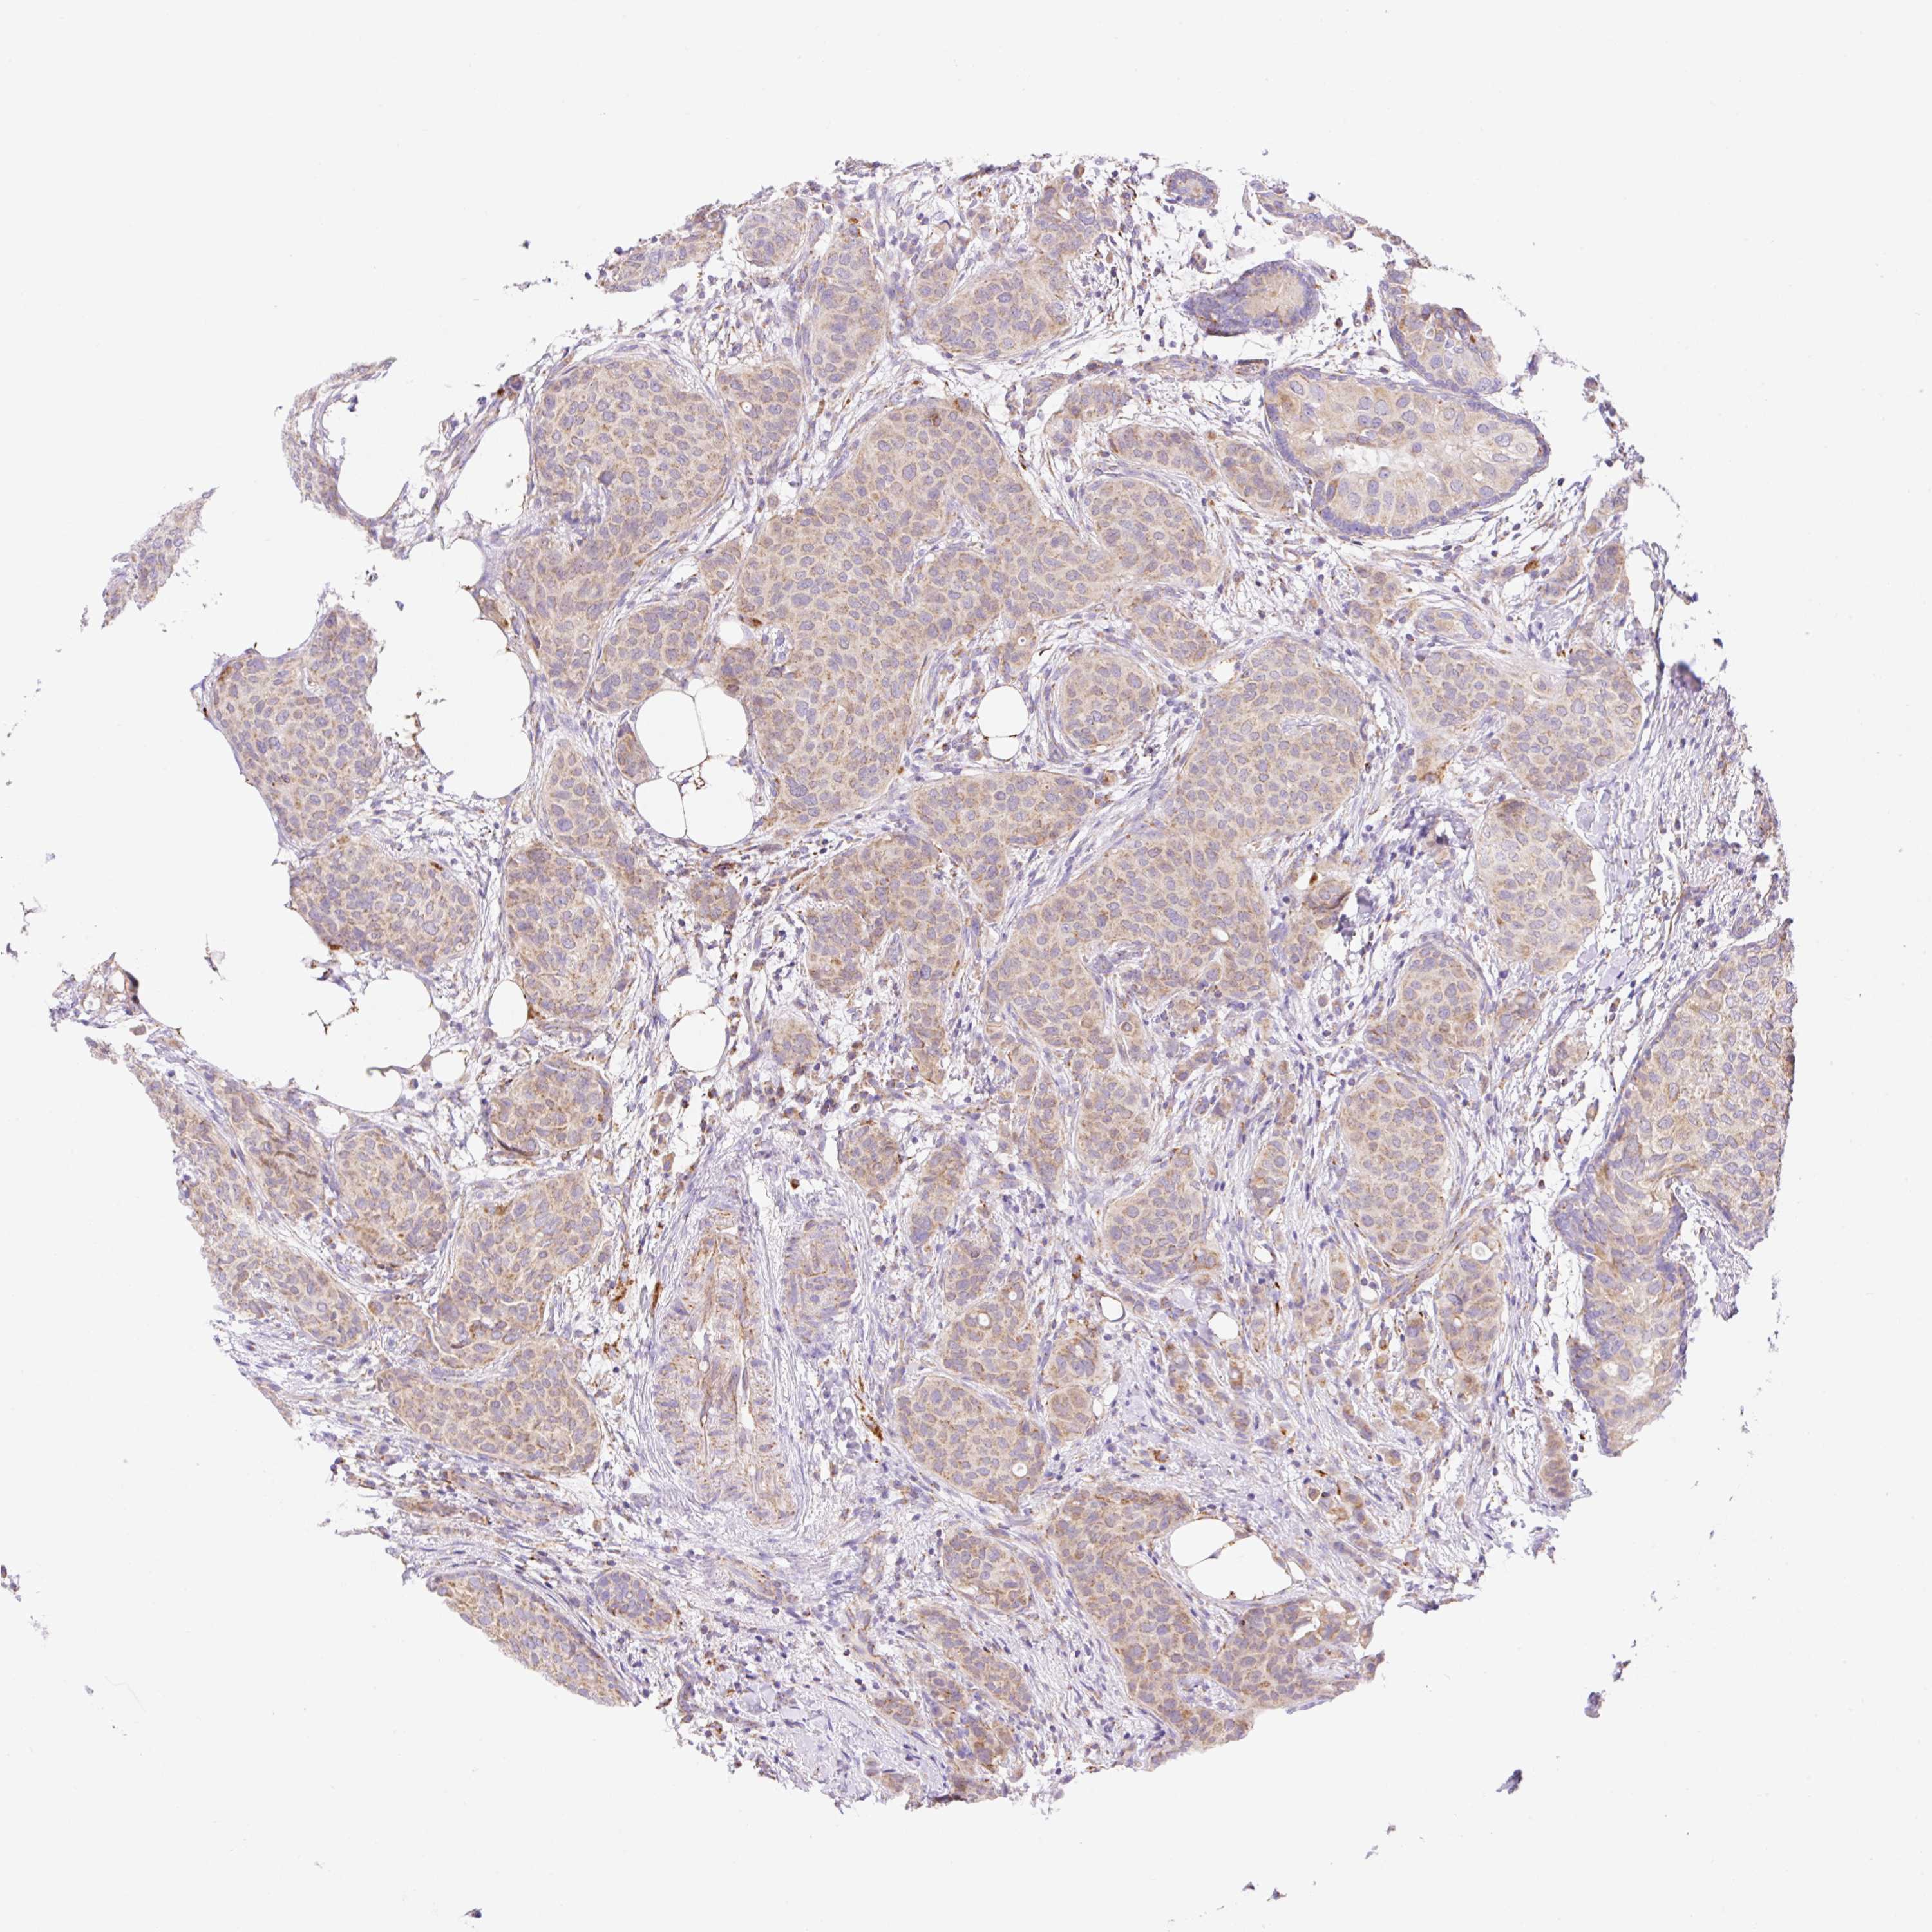

CANCER BREAST CANCER Show tissue menu

Breast cancer

Human cancer